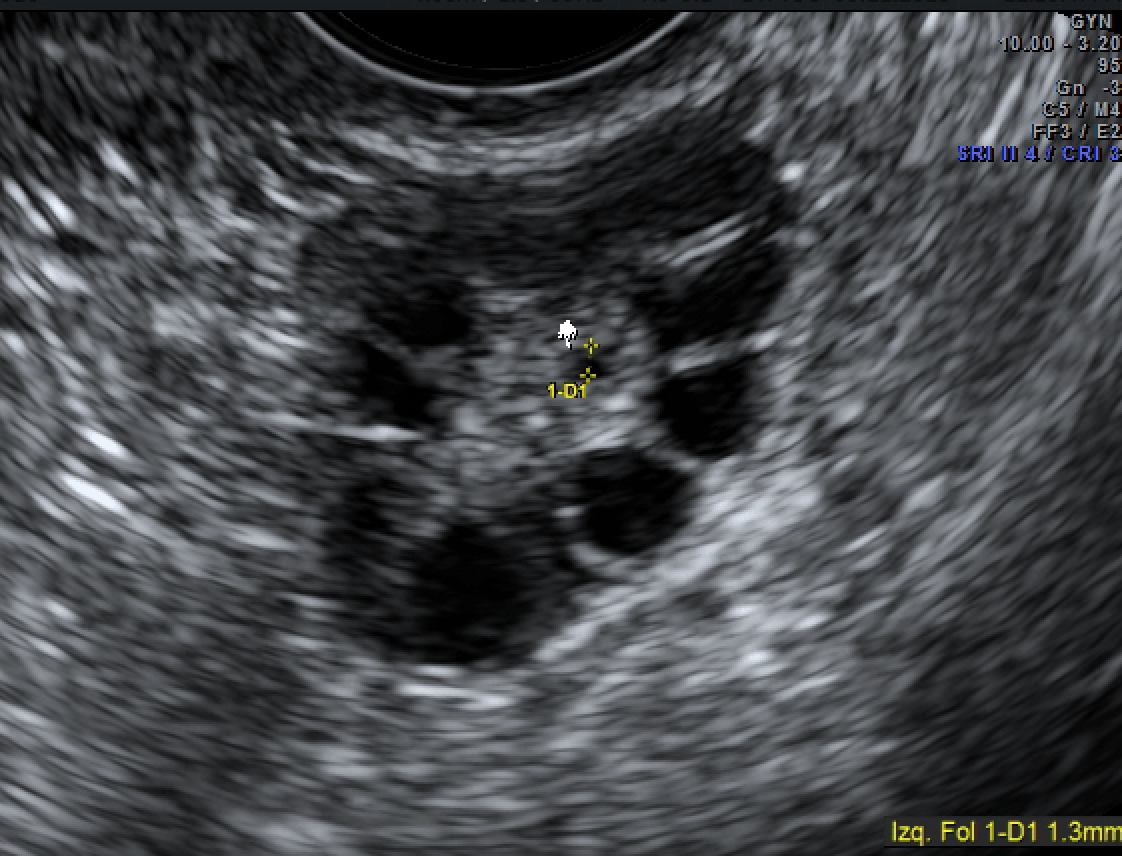

WebUna mujer con baja reserva ovárica no presenta síntomas, a priori, por lo que para conocerla, debes ir a tu ginecólogo. Tu médico mediante una ecografía vaginal podrá. WebAunque es posible lograr un embarazo natural teniendo una reserva ovárica baja, en ocasiones es preciso recurrir a tratamientos como: Estimulación ovárica .. WebTestimonio 1: Baja reserva ovárica. El dia que me enteré que para tener hijos necesitaría ayuda nunca lo olvidare. Todo empezó hace ya 11 años, yo tenía 27. WebBaja reserva ovárica: 10 datos que te interesan. Si estás intentando quedarte embarazada y te han diagnosticado una baja reserva ovárica, es probable que intuyas que algo no va. WebTestimonio de embarazo natural con baja reserva ovárica con acupuntura. En nuestro centro venimos atendiendo, con éxito, casos de pacientes con baja reserva ovárica y. WebCon baja reserva ovárica y más de 40 años, es muy difícil embarazarse de manera natural, Francisco José. Tendréis que acudir a una clínica especializada para. WebEl problema es que algunas mujeres tienen una baja reserva ovárica siendo jóvenesy mucho antes de lo previsto. En Equipo Juana Crespo somos especialistas en.